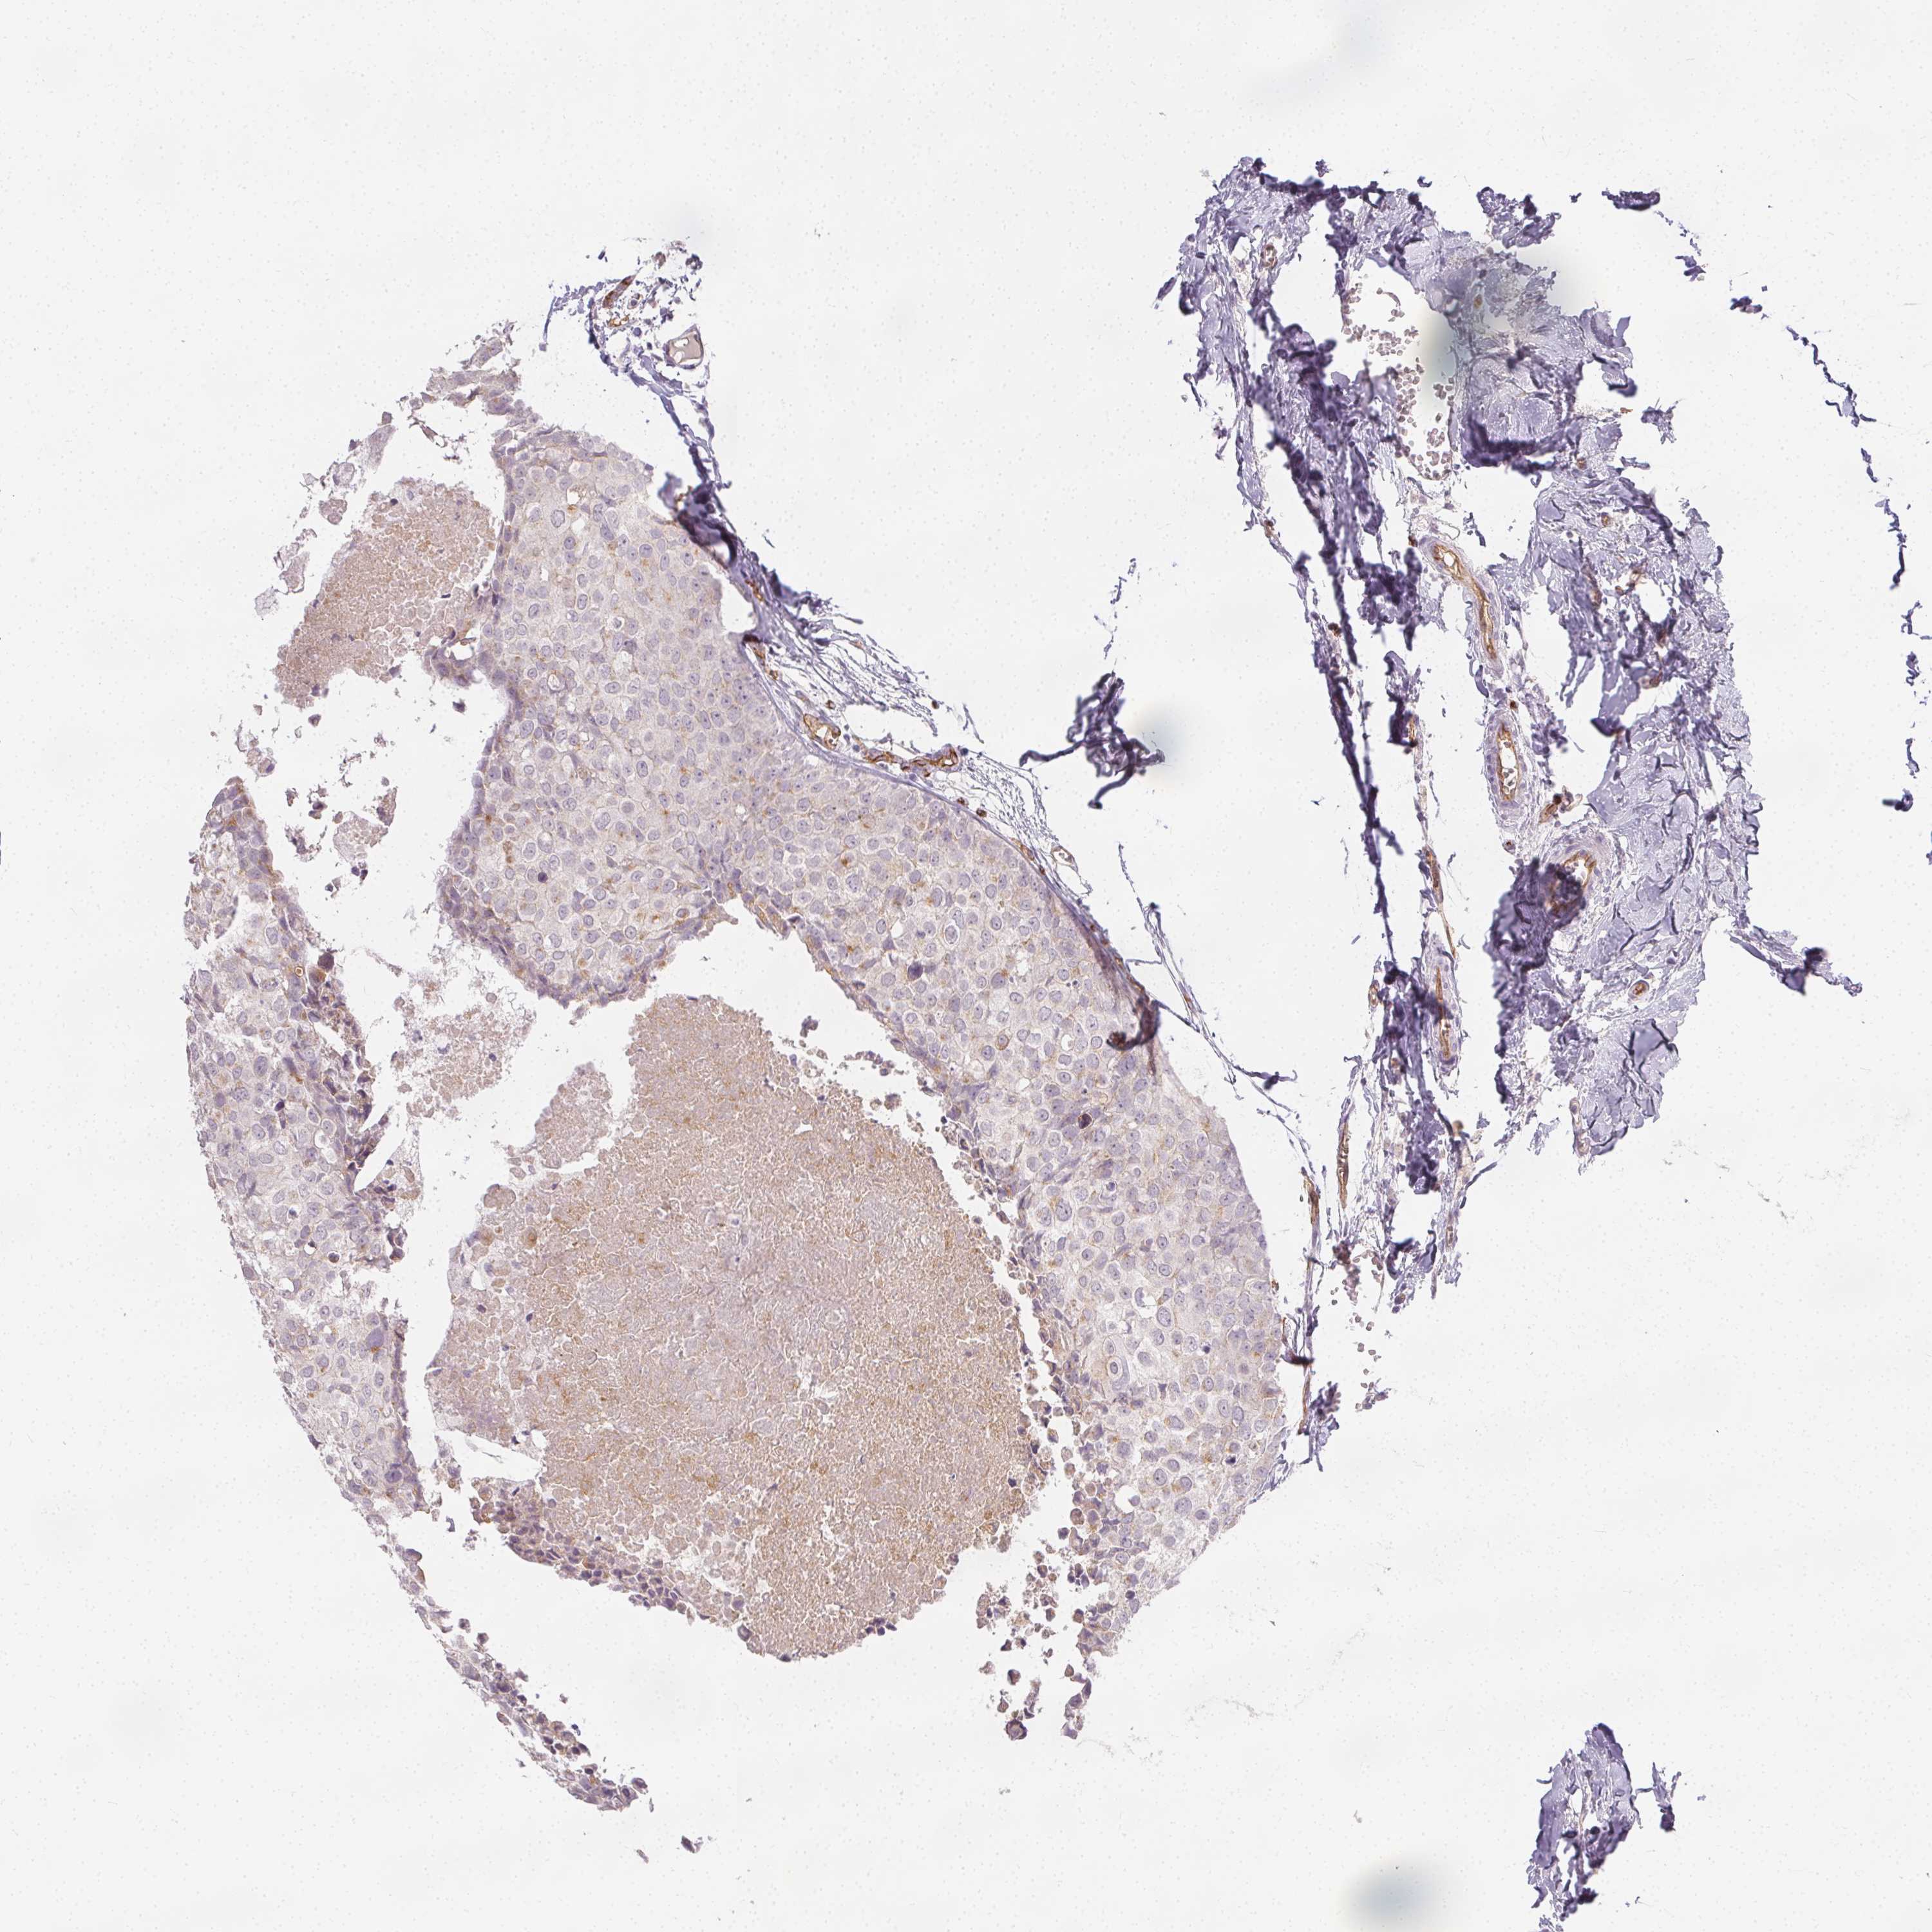

BRCA TCGA BRCA VALIDATION PROTEIN EXPRESSION

ANTIBODIES

AND

VALIDATION